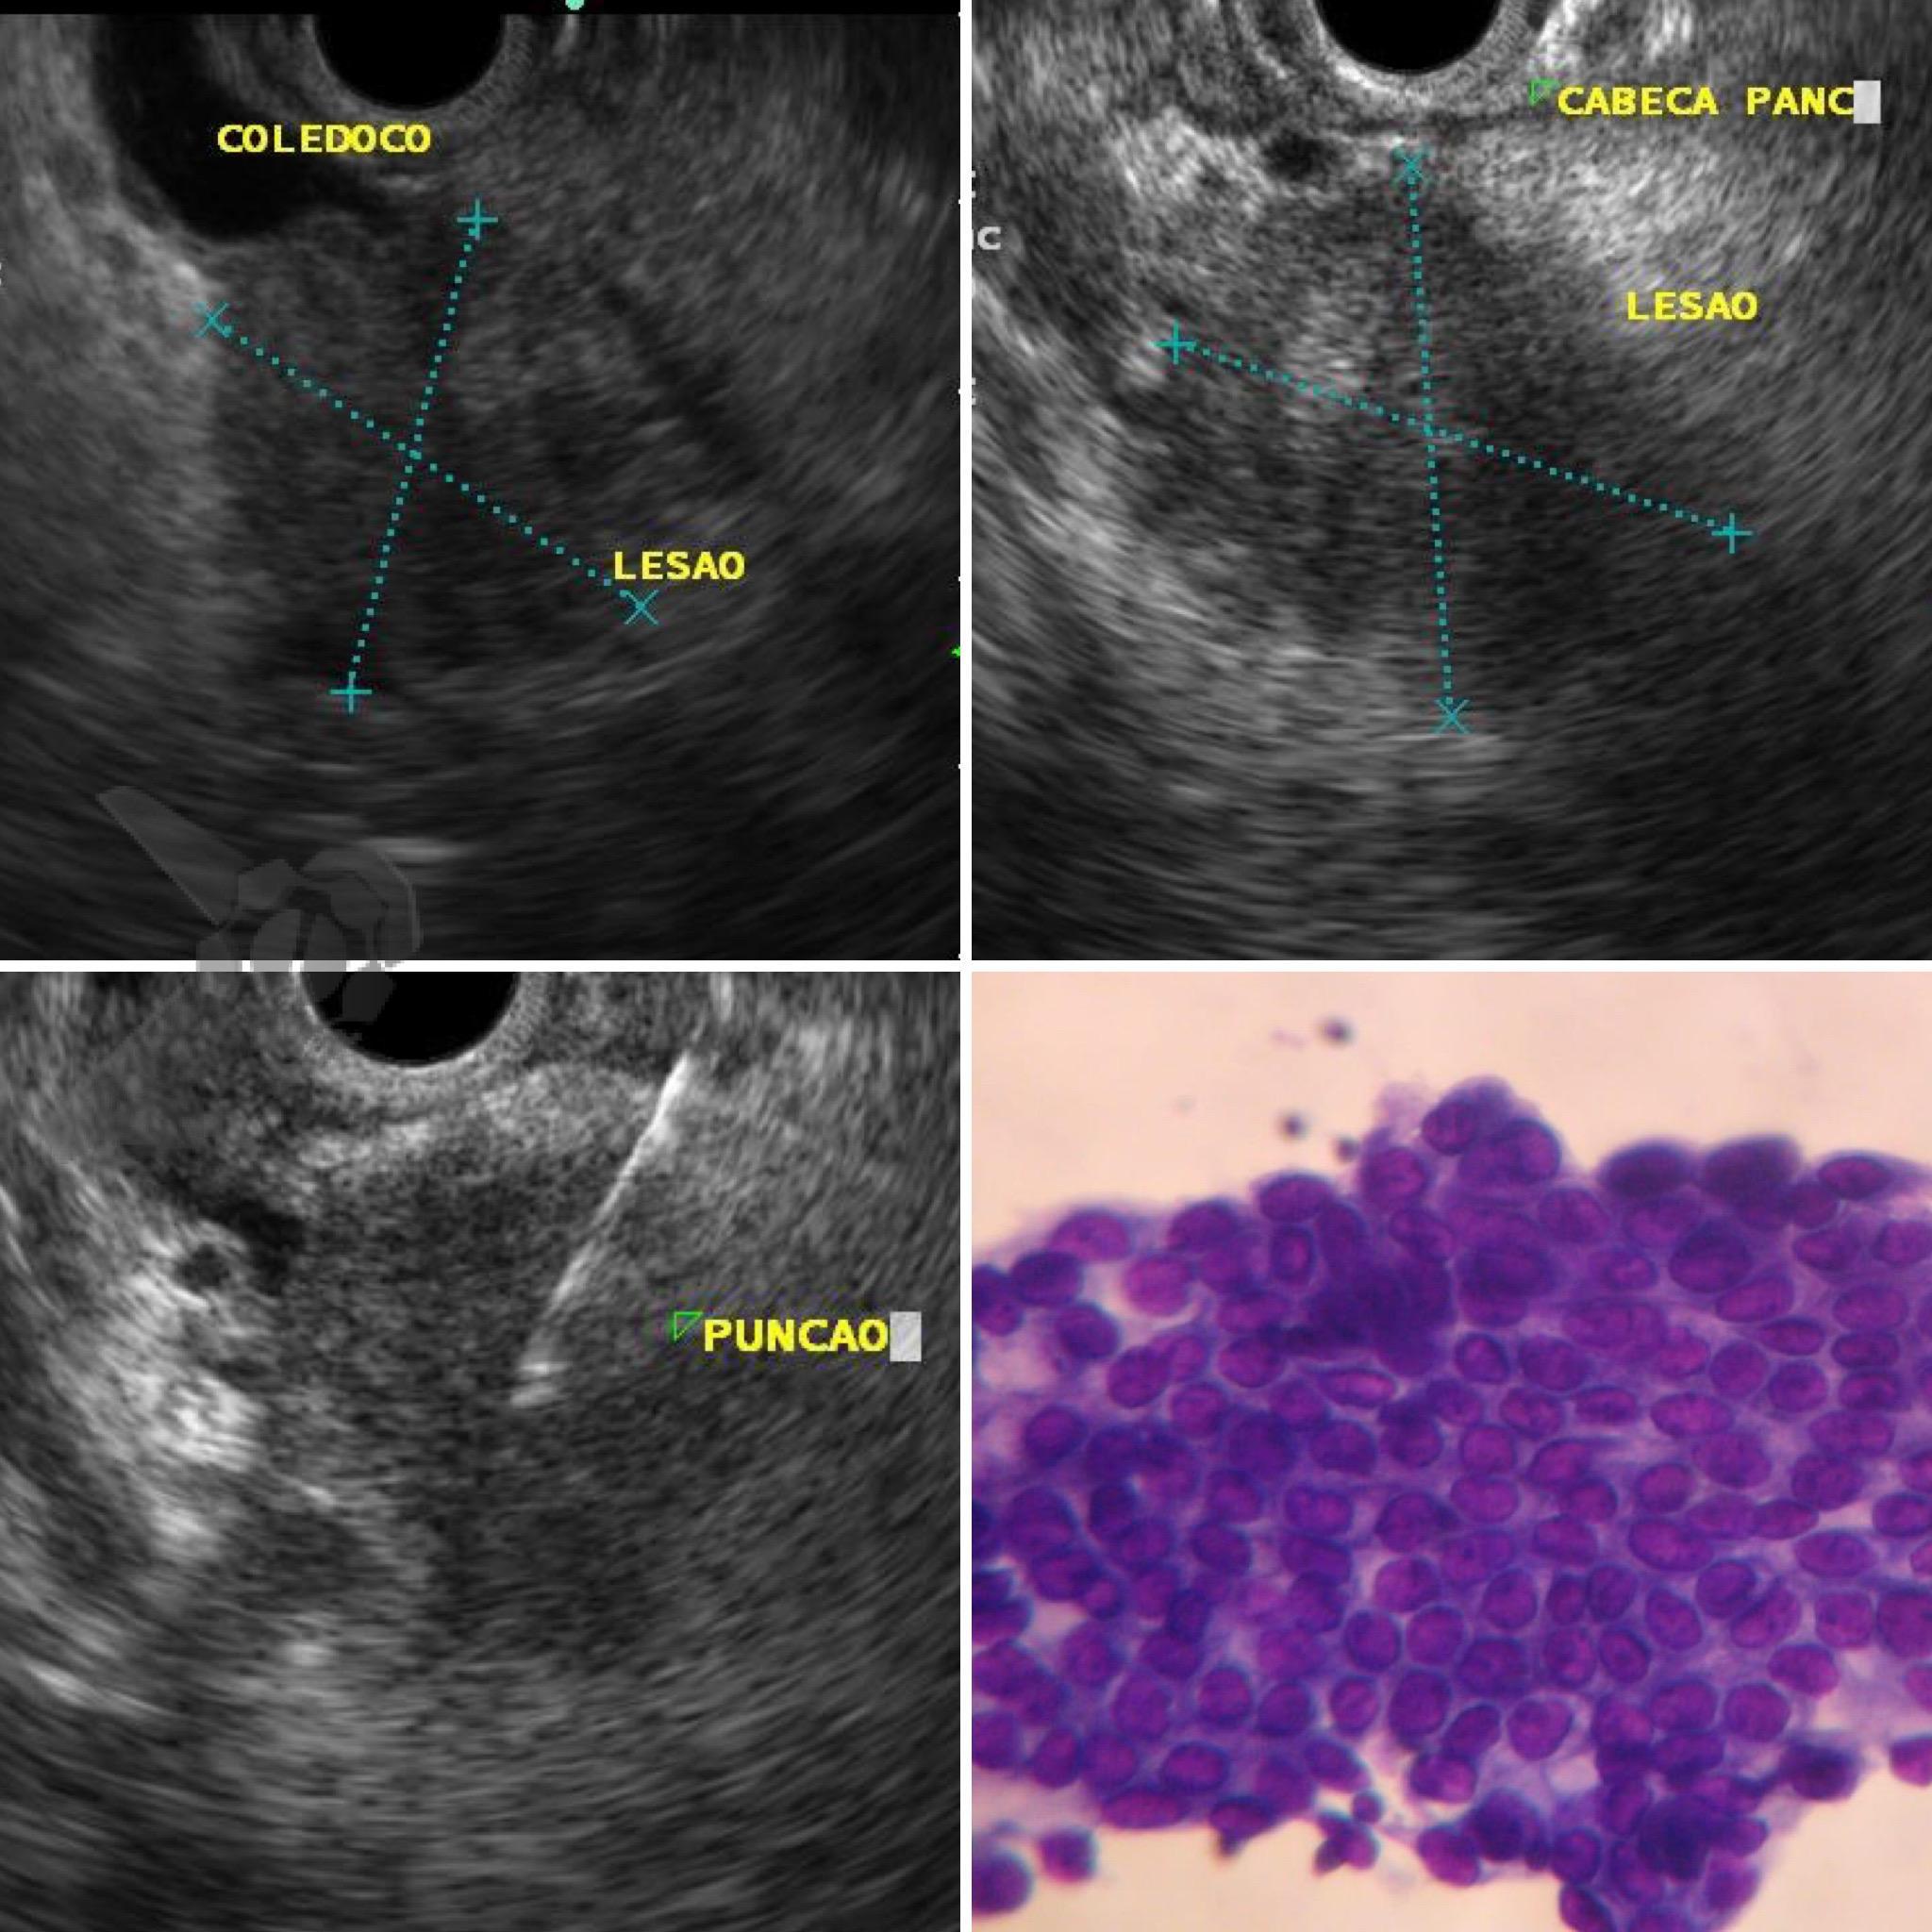

Durante investigação constatou-se à RNM de abdome uma volumosa massa sólida em topografia de cabeça pancreática com invasão de veia mesentérica.

Posteriormente submeteu-se à Ecoendoscopia com punção da lesão que confirmou se tratar de Adecocarcinoma mal diferenciado. Em virtude do estadiamento e condições clínicas do paciente, foi definido em avaliação multidisciplinar por tratamento oncológico clínico (não cirúrgico) com drenagem da obstrução biliar maligna (OBM) através de prótese metálica autoexpansível (PMAE).